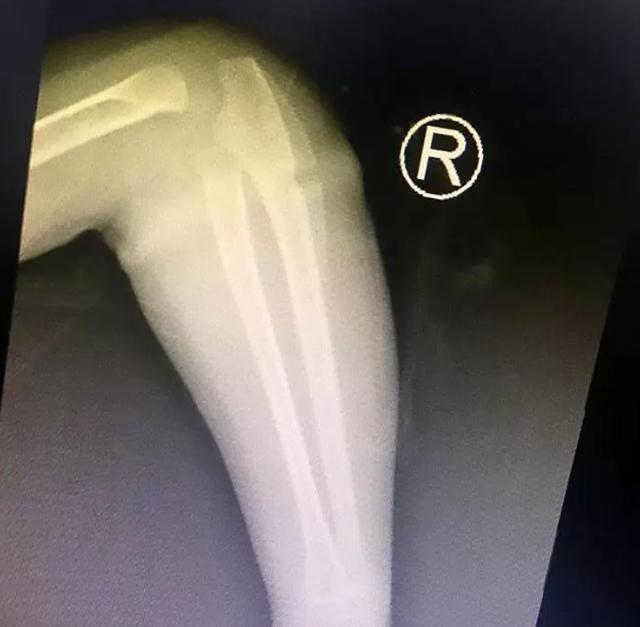

Ảnh chụp X-quang cho thấy có dị vật trong cánh tay bé gái.

Ảnh chụp X-quang cho thấy, quả thật bên dưới cánh tay của Le Le có "vật thể lạ". Ngay sau đó, các bác sĩ đã phẫu thuật và lấy ra một chiếc dây thun màu vàng ngay dưới lớp da tay của bé gái. Họ đoán rằng, bé gái đã đeo chiếc dây thun này suốt một thời gian dài nhưng ông bà không hề biết. Vì chiếc dây thun có tính co giãn nên nó đã "ăn sâu" vào lớp da dẫn đến tình trạng sưng tấy quanh cánh tay.